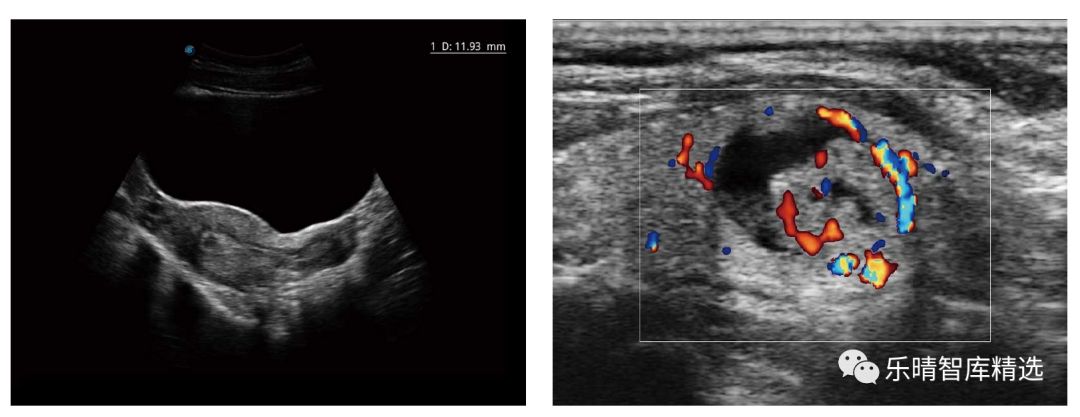

医用超声诊断仪最早诞生于20世纪60年代,早期只能获取人体组织的结构信息,简称B超,通过黑白的灰阶图像来显现不同组织对超声波的反射强度,因此又称为黑白超。

直到20世纪80年代,通过超声波的多普勒原理和技术,超声诊断仪不仅可以显示结构信息,还可以显示人体内的血流信息,并且通过红蓝两种颜色来区分血流的方向,彩超-彩色多普勒超声诊断仪正式诞生,彩超的时代正式到来(由于黑白超目前只占整个市场容量不到10%份额,因此下文中的超声多指彩超)。百度搜索“乐晴智库”获得更多行业报告。

从传统的形态学诊断发展到功能诊断,如弹性成像、组织斑点追踪、超声造影、微观研究等。

比如超高端的心脏彩超,在二维图像和彩色血流信息的基础之上,某些进口企业把特殊分析软件加在彩超里面,包括心肌运动、心脏在有局限性的梗死的状态下、心肌功能的衰退等,机器诊断的层面就是由单纯的图像诊断上升到一个功能诊断,行业出现了质的飞跃。